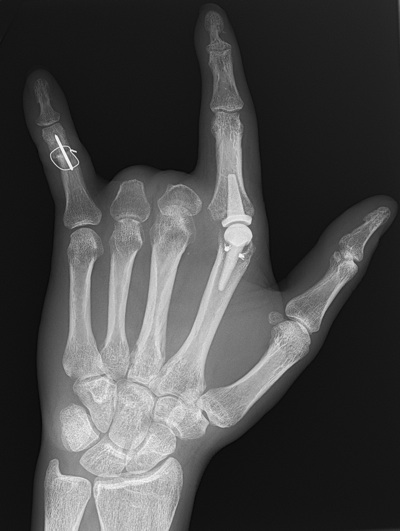

It was always our contention that the Hook'em Horns gesture was merely the sign of a careless carpenter ordering 4 beers.

I don't know if the person above is actually from Austin, but it's possible...